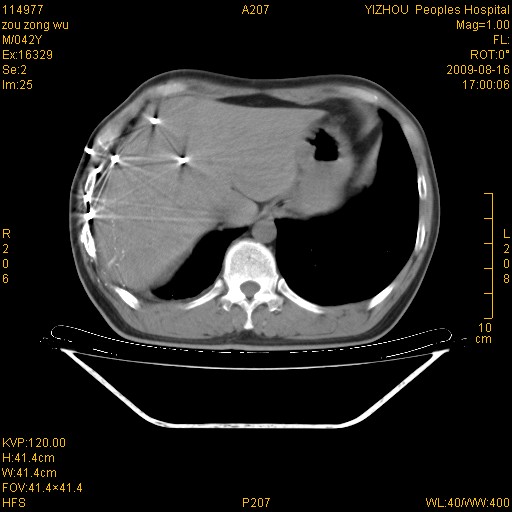

以下是引用zjzjr在2009-8-17 10:42:00的发言:[br]右侧间质性肺炎伴纤维化,右肺下叶肺囊肿伴感染(不除外外伤后引起),右肺野及胸壁软组织\\肝内见多发斑点状,中枪了吧.右侧胸膜肥厚\\粘连.